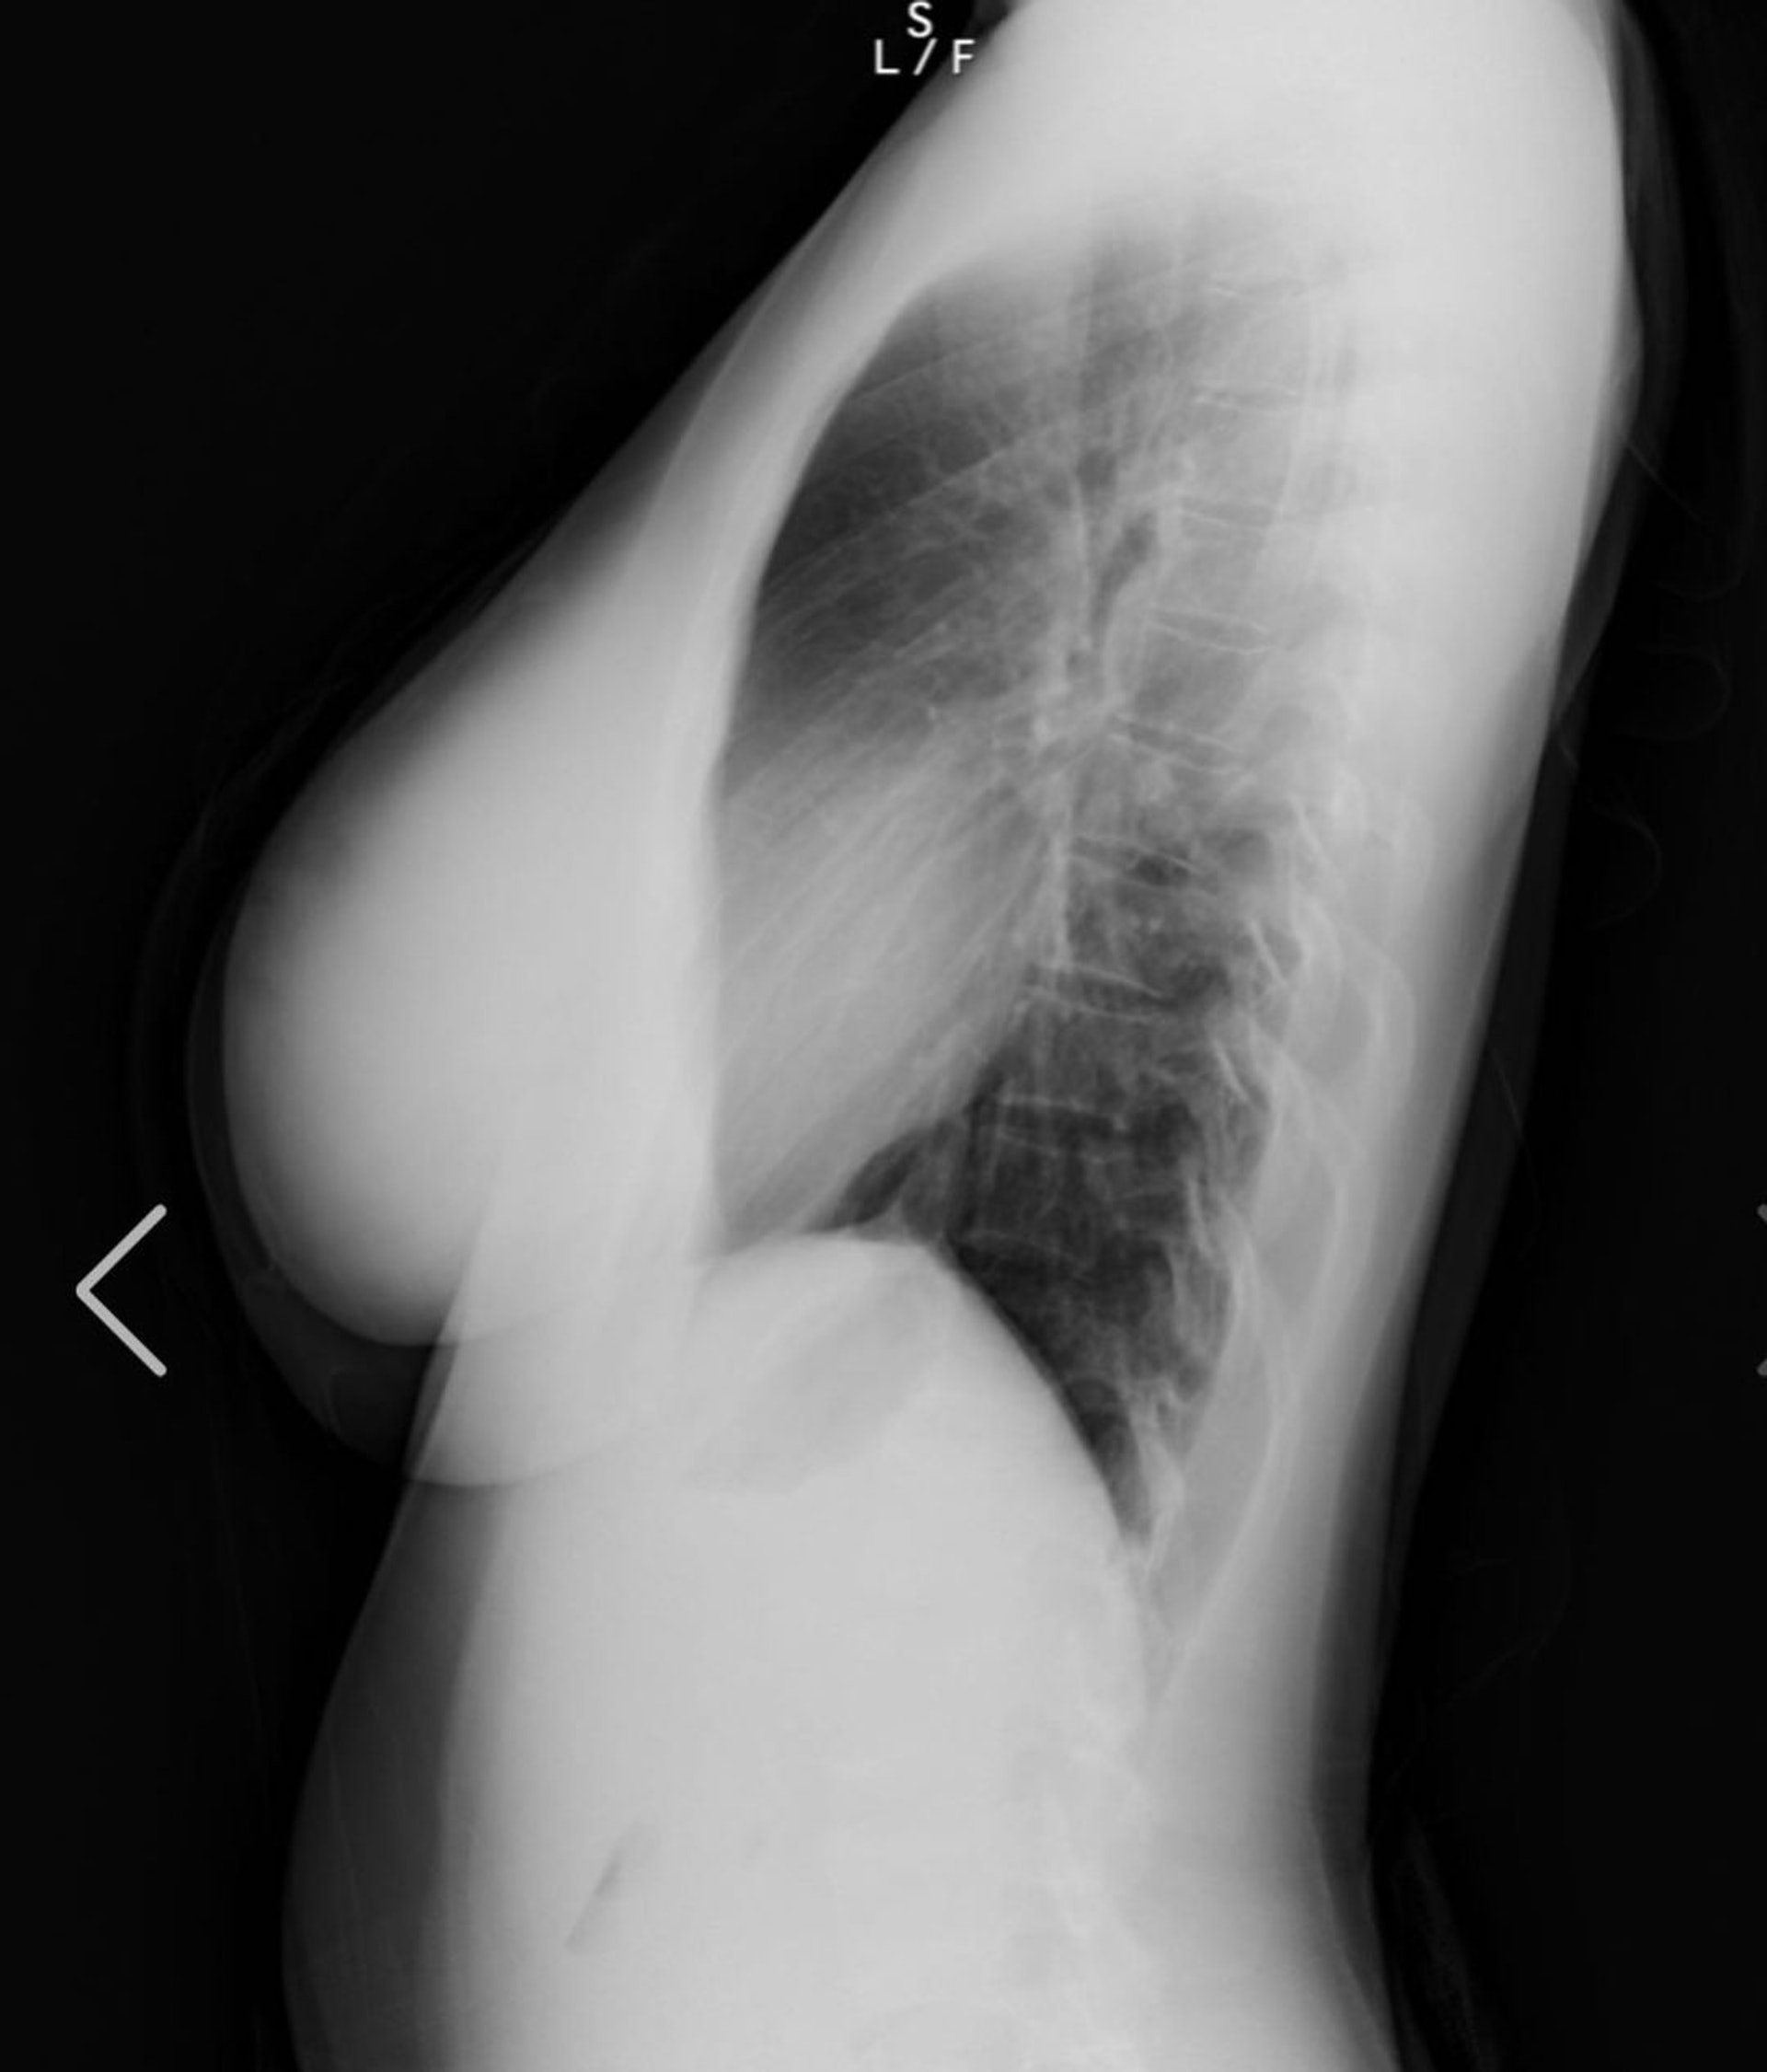

▲在她自己放出來的x光照片顯示,自己完完全全是純天然的,而右胸的黑影只是胃泡,請各位不要再懷疑她了